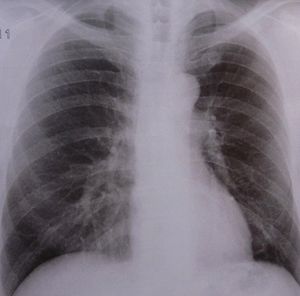

Lungen-Röntgen: gezieltere COPD-Therapie kommt (Foto: pixelio.de, Dieter Schütz) |